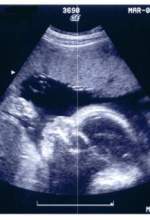

Defenses for abortion come in three varieties: medical, philosophical, and emotional. The first two are fairly easily dealt with, even if people do not amend their positions. The arguments are either true or false, sound or unsound. The last however, is much more problematic. Emotional arguments … [Read more...]